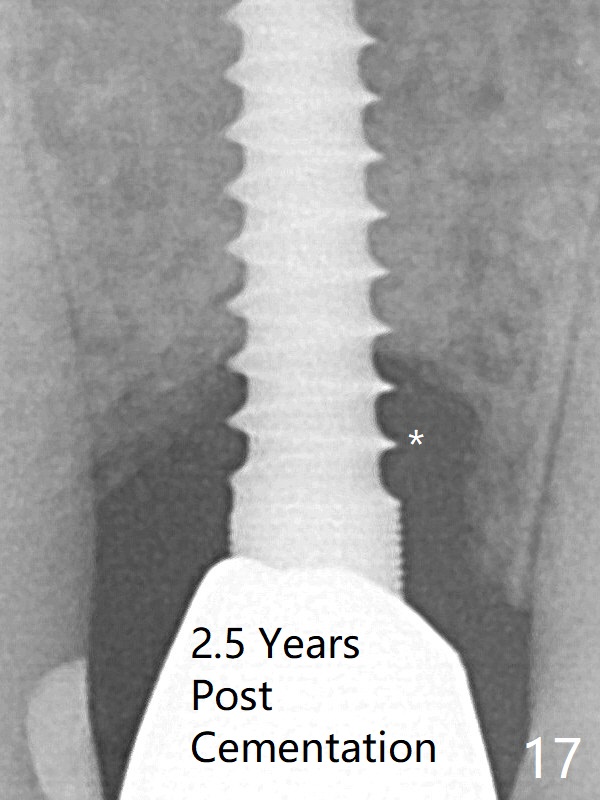

The peri-implant space (Fig.3) is filled with bone graft (Fig.4 *). The apical portion of the socket appears to have reduced 4 months postop (Fig.14). When the patient returns 1.5 years post cementation, there is increased bone density next to the coronal portion of the implant, equivalent to the bone graft (Fig.15 *). The crestal bone loss remains 2.5 years post cementation (Fig.17 *), although there is no sign of periimplantitis. Oral hygiene is poor.